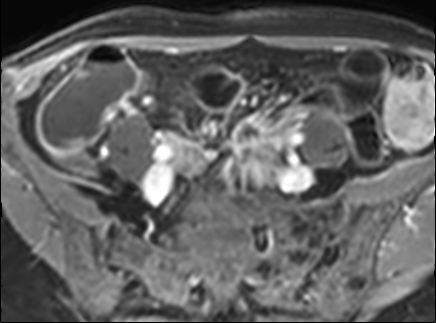

Kiểu ngấm thuốc phân lớp tại trực tràng kèm một ít mờ mỡ xung quanh trên hình ảnh T1 axial sau tiêm thuốc tương phản từ (mũi tên). Tình trạng viêm liên tục với kiểu ngấm thuốc đồng nhất có thể thấy tại đại tràng sigma (mũi tên xanh lá). Ngoài ra, có một nang phần phụ bên phải với viền ngấm thuốc (đầu mũi tên).

Kiểu ngấm thuốc

phân lớp

Kiểu này gợi ý hoạt động bệnh nặng hoặc bệnh mạn tính kéo dài (4,5).

Hình ảnh ba lớp được tạo ra do niêm mạc và thanh mạc ngấm thuốc mạnh trong khi lớp giữa không ngấm thuốc, bao gồm lớp dưới niêm mạc và lớp cơ.

Lớp giữa này có thể chứa mỡ, phù nề hoặc mô xơ.

Có thể phân biệt các thành phần này bằng chuỗi xung T2 có fat-sat.